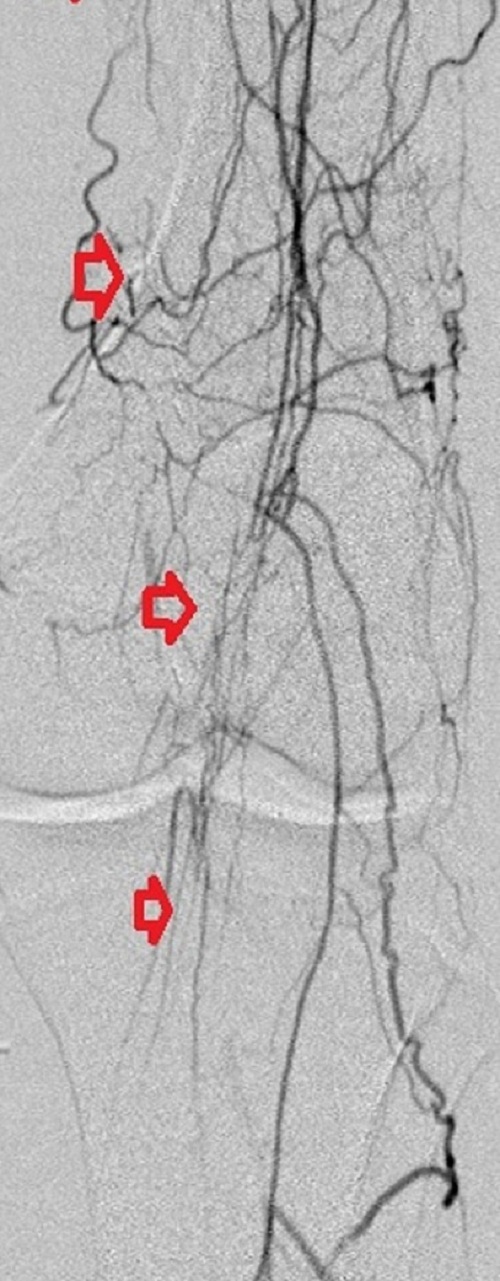

Key to images:

Bottom panel: Post intervention run-off arteriogram of the left lower extremity showing, from left to right, the proximal and distal segments of the re-opened left femoro-popliteal bypass (red arrows on images 1, 2, and 3). Contrast the full-column opacification of the below-knee left popliteal artery, arrowed blue on the 3rd image, and the enhanced visibility of the three-vessel subpopliteal domain to their vestigial appearances on the pre-intervention images, when they were poorly fed through collaterals.

When blood flow into or out of a bypass fails, it thromboses and its salvage includes gaining access into it and removing the clot in addition to determining the reason for its failure. Such clot removal may be mechanical, as is frequently the case in acute graft failure, or through thrombolysis, as is the case in later failures. The above images illustrate the later scenario in which the patient presented about 1 year after a left femoropopliteal bypass was fashioned for them. I crossed into the lumen of the bypass conduit from a right common femoral arterial puncture and advanced an infusion cather into it for overnight continuous alteplace infusion following a bolus dose. (I favor 5 to 10 mg of alteplace bolus, followed by continuos infusion at 0.5 mg per hour, in company with fixed unfractionated heparin infusion at 500 units to 600 units per hour after a bolus dose of 3000 units to 5000 units). In this case the bypass proved to be a vein conduit connecting the left common femoral artery, proximally, to the mid popliteal artery, distally, without intimal hyperplasia. The cause of the failure was diminished inflow due to left iliac disease.The final runoff images reveal a three-vessel tibial domain continuous with a near-normal plantar arch.